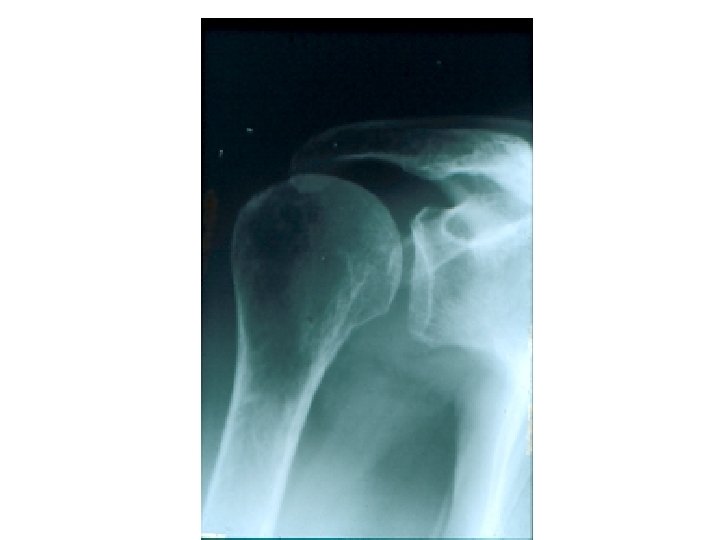

SEMIOLOGIE DE L’EPAULE IV – DIAGNOSTIC ETIOLOGIQUE A – Atteintes périarticulaires B – Rétraction capsulaire de l’épaule (épaule gelée – algodystrophie) C – Arthroses de l’épaule D – Arthrites – rhumatismale (contexte) – infectieuse +++